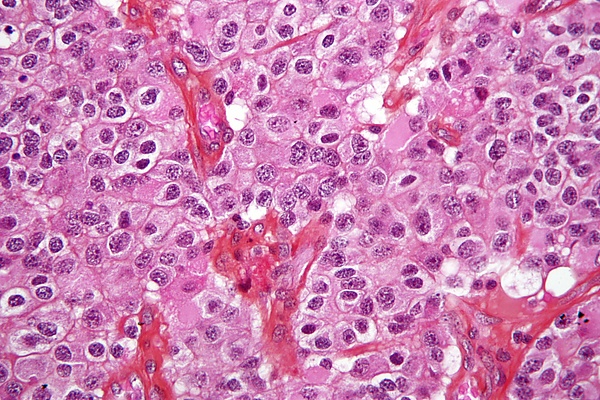

Микроскопически олигодендроглиомы характеризуются пластами мономорфных клеток малого и среднего размера со сферическими ядрами, окружёнными светлым перинуклеарным ободком. Характерным признаком этих опухолей является сеть тонкостенных капилляров, описываемая как сосудистый рисунок типа «куриной лапки». Часто выявляются рассеянные кальцификаты и псаммомные тельца. На поверхности опухоли иногда наблюдаются миелиноподобные структуры, хотя они не соответствуют критериям истинных миелиновых оболочек. Анапластические олигодендроглиомы высокой степени злокачественности демонстрируют повышенную клеточность, выраженную ядерную атипию и высокую митотическую активность. Данные опухоли также могут проявлять микрососудистую пролиферацию, увеличение плотности сосудов и наличие некрозов, что отражает ускоренный рост и пролиферацию опухолевых клеток[4].